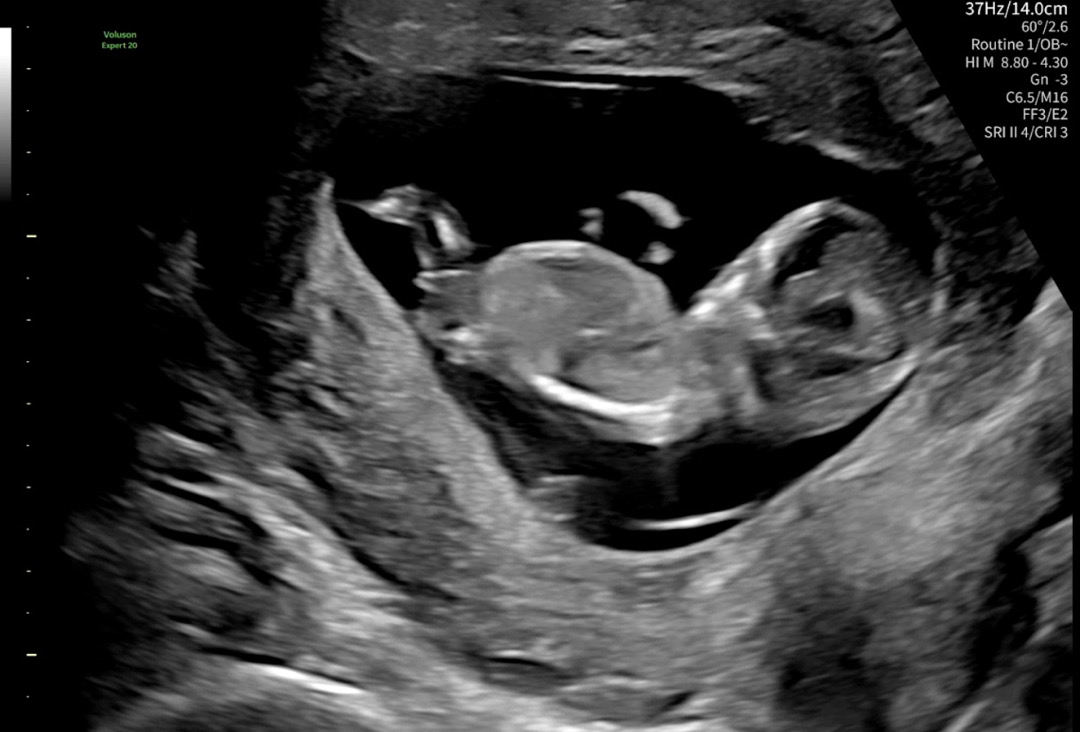

12주차 각도법 확인 가능할까요?

지피티는 아들 제미나이는 딸이라는데.. 어때보이나요?!…